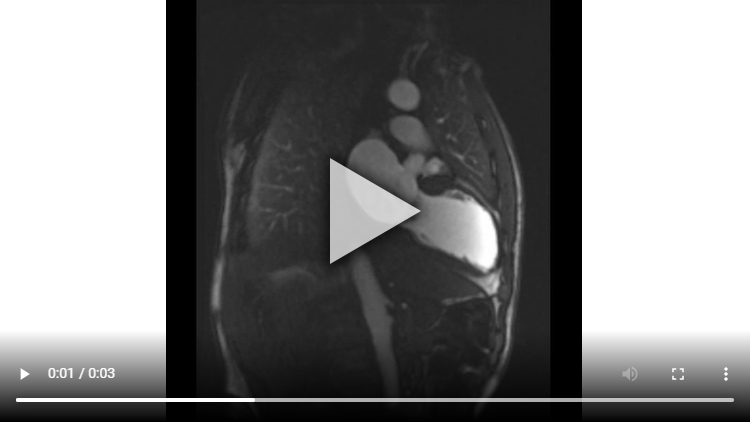

Figure 3A : Séquence de rehaussement tardif - Coupes petit-axe

Présence d’un large rehaussement tardif sous-endocardique de 8 à 9 segments sur 17 avec un réhaussement transmural (100% de transmuralité) dans la quasi-totalité des segments. Ainsi, si l’IRM cardiaque avait été réalisée à plus de 4 semaines de la phase aiguë nous aurions pu conclure avec certitude à une absence de viabilité.

Cependant, le fait d’être à seulement 2 semaines de la phase aiguë ne nous permet pas de conclure avec certitude à la non-viabilité de cet IDM

Enfin, bien que l’amincissement de la paroi (< 6 mm dans les recommandations en échocardiographie) et l’akinésie soit très en faveur d’une absence de viabilité, plusieurs études ont montré que certains patients pouvaient malgré tout présenter un IDM viable (avec alors un rehaussement tardif < 50% sur l’IRM réalisée à plus de 4 semaines de la phase aiguë).

Aucun thrombus intra-VG n’est visualisé sur ces séquences de rehaussement tardif. Un thrombus serait apparu sous la forme d’une masse en hyposignal (noire) au niveau de l’apex VG par exemple.